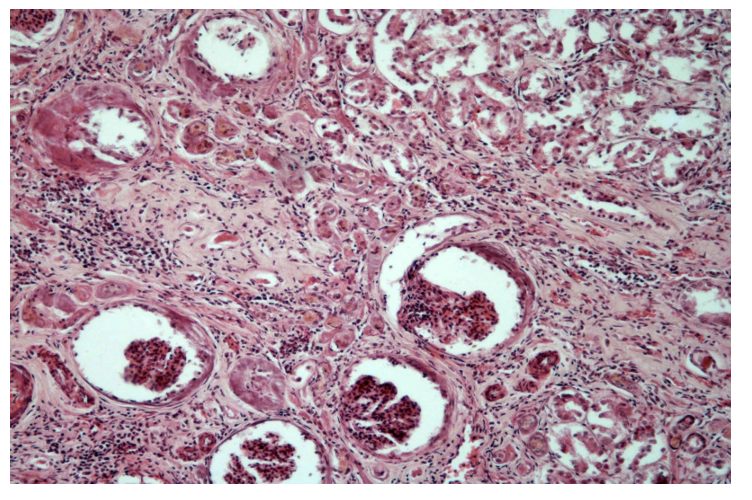

164. Glomerulonephritis chronica

Description: Most glomeruli are morphologically changed. They show thickened Bowman’s capsule which press on glomeruli, causing atrophy (periglomerulitis chronica). Many vessels of glomeruli are hyalinized. Some glomeruli are fibrotic (sclerosis). A large number of tubules have atrophy and others are dilated and become filled with eosinophilic casts. Interstitium is dilated and infiltrated by chronic inflammatory cells (lymphocytes, plasma cells, macrophages, rarely neutrophils).

Etiology: Chronic glomerulonephritis is caused by a long-term inflammation of glomeruli. The initial cause can be viral, bacterial, parasites, neoplasms, autoimmune disease or genetic predisposition.

Pathogenesis: The formation of immune complexes stimulate production of proteins which are chemotactic to neutrophils. These neutrophils infiltrate and damage the basement membrane and afterwards, monocytes infiltrate the glomeruli and continue damaging the glomeruli. When the lesion is severe and prolonged, the glomeruli turns hypocellular and non-functional (glomerulonecrosis)